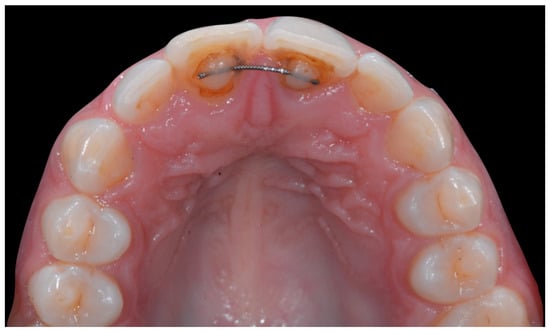

The occlusal views provide additional relevant information (Figure 9 and Figure 10). A maxillary retainer was present on 11 and 21 only and a difference in visibility of the vestibular surfaces (differential torque) on these same teeth was noted.

Intermediate wire syndrome. Occlusal view.

In the mandible, the retainer was broken distal to 42 and, despite being intact on 33, this tooth had increased visibility of its vestibular surface compared to its contralateral tooth (differential torque). Finally, teeth 31 and 41 also showed a difference in the visibility of their vestibular surfaces (differential torque). Ultimately, the patient was diagnosed with an X-effect wire syndrome on 21, an X-effect wire syndrome on 41, and a Twist-effect wire syndrome on 33.